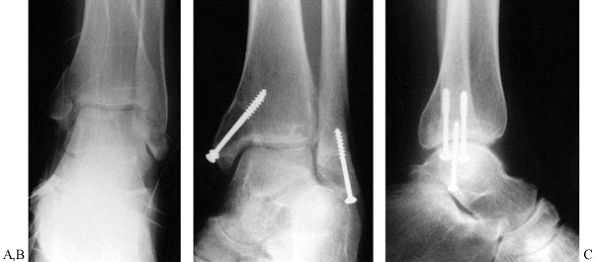

![]() |

Figure 25.16. A: Preoperative anteroposterior radiograph of a supination-adduction type fracture or Weber type A. B,C: Postoperative radiographs illustrate the usex of an axial lag screw for the avulsion fracture of the distal fibula.

Figure 25.17. A:

Anteroposterior and lateral radiographs of a SER type lateral malleolar fracture. Notice the medial clear space widening consistent with medial ligamentous injury and dynamic instability. B: Postoperative radiographs demonstrating fixation with a posterior, antiglide technique. C: Radiographs 1 year postoperatively demonstrating osseous union and anatomic restoration of the ankle mortise. |

Figure 25.18. A: Anteroposterior and lateral radiographs of a SER type bimalleolar fracture. B:

Postoperative radiographs demonstrating various fixation techniques including stacked one-third tubular plates, push-pull screw (empty screw hole proximal to plate), and 2.7-mm screws utilized to secure small medial malleolar fragment. |